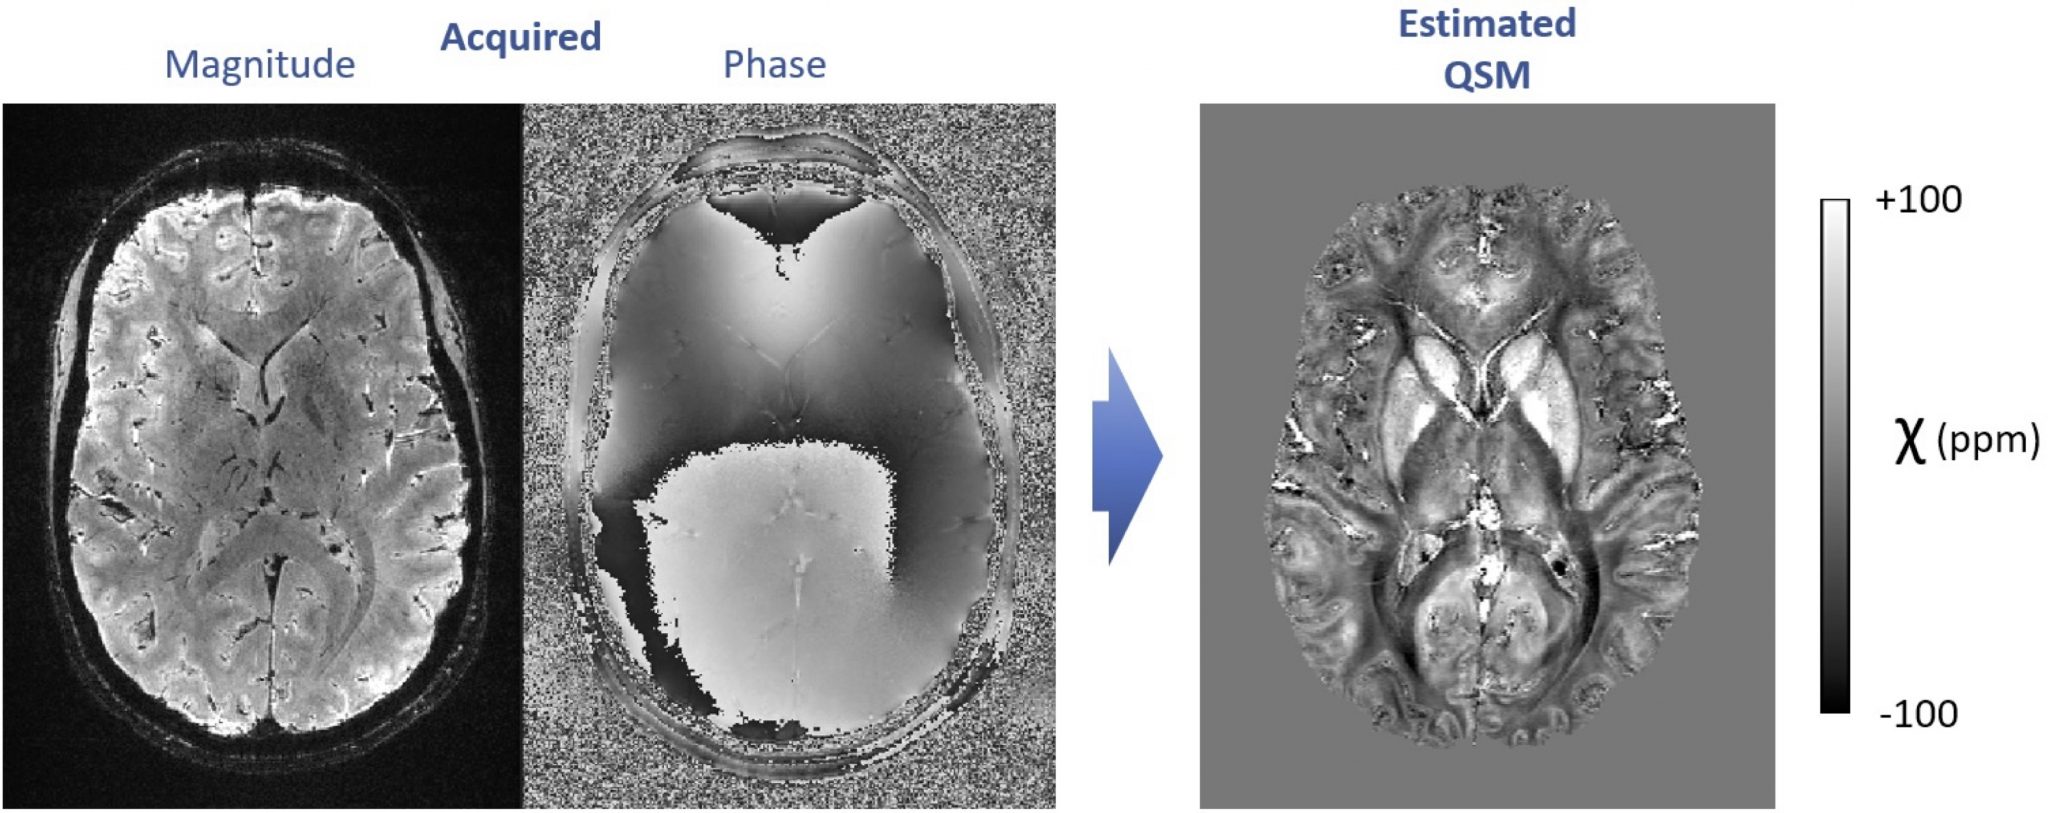

7. High-resolution quantitative susceptibility mapping with 7T MRI

Using dedicated image acquisition and processing techniques, MRI allows mapping the distribution of magnetic susceptibility in living tissues, non-invasively and without injected contrasts. Magnetic susceptibility is currently under research for numerous clinical applications such as the detection of microbleeds, calcifications and abnormal iron metabolism, in the brain as well as other organs.

We work on improving quantitative susceptibility mapping (QSM) approaches at 7 Tesla, to generate exquisitely detailed, sub-millimeter resolution images. To achieve this goal, the topics of interest include the mitigation of interference from motion, the reduction of effects from blood vessels and blood flow, and the improvement of QSM reconstruction techniques based on acquired field maps (ill-posed inverse problem). The solutions include cutting-edge approaches in model-based image processing and/or deep learning.

Within this range of topics, diverse MSc projects can be planned and flexibly adapted to the student’s background and interests. Motivated students are encouraged to contact us to discuss available projects. These projects are held in collaboration with CSEM.